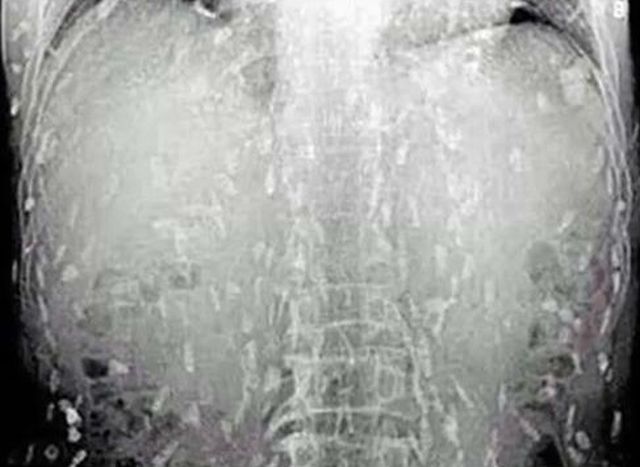

Pacientul a fost supus unei radiografii, iar rezultatele au scos la iveală o serie de imagini şocante! Corpul bărbatului era infestat cu viermi, motiv pentru care el a prezentat simptomele îngrijorătoare.

Medicii au ajuns la concluzia că acest lucru s-a întâmplat din cauza consumului de sushi, în special de sashimi, unul dintre cele mai fine preparate din bucătăria japoneză. Se pare că una din bucăţile de peşte crud pe care bărbatul le-ar fi consumat, a fost infectată cu "cestoda", o clasă de viermi paraziţi. Genul acesta de viermi pot trăi ani de zile în organismul uman, să se dezvolte până la o lungime de 15 metri şi să ameninţe viaţa victimei.